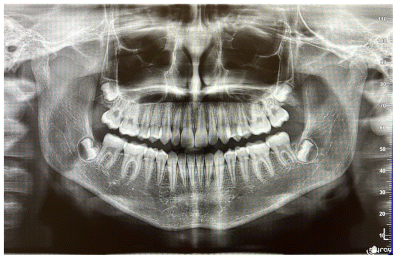

The patient was a young female presenting with a Class III dento-skeletal malocclusion, which was treated using the AMCOP® TC appliance. A comprehensive diagnostic protocol was carried out both before and after treatment, including orthopantomography (Figure 2–3), postero-anterior teleradiography (Figures 4, 5), latero-lateral cephalometric radiography (Figures 6, 7), cephalometric analysis (Tables 1, 2), as well as extraoral (Figures 8, 9) and intraoral photographs (Figures 10, 11). The extraoral examination revealed an edge-to-edge incisal relationship and the presence of a midline diastema. Pre-treatment cephalometric analysis (Deltadent® Lana, Bolzano, Italy) confirmed the diagnosis of a skeletal Class III malocclusion. The treatment plan involved the use of the AMCOP® TC appliance. The patient was instructed to wear the device for two hours in the afternoon and throughout the night for the first six months, followed by nighttime use only for an additional six months. Upon completion of the treatment, the patient achieved a Class I occlusion, with correction of both overjet and overbite. Additionally, the device facilitated tongue re-education and contributed to the postural realignment of the first cervical vertebra.